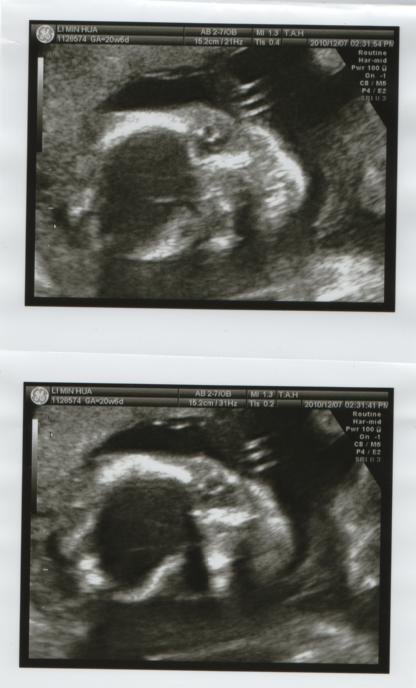

高層次超音波只有這樣的照片?!

今天到醫院做了高層次超音波,因為寶寶姿勢不好→翹屁股趴著

半小時結束後拿到這樣四張臉部照片,其餘的手腳、大腿、小腿的照片都沒有

若是這樣應該也要提供不一樣的部位吧?!跟醫生反應得到的答案是"姿勢不好"?所以只提供照的清楚的臉...

今天的高層次超音波,在半小時快速講解中結束了,拿到了這樣4張照片

結果拿到的只有這四張高層次"臉部特寫"大頭照...因為看到的都是骨骼,感覺還挺像外星人的說....